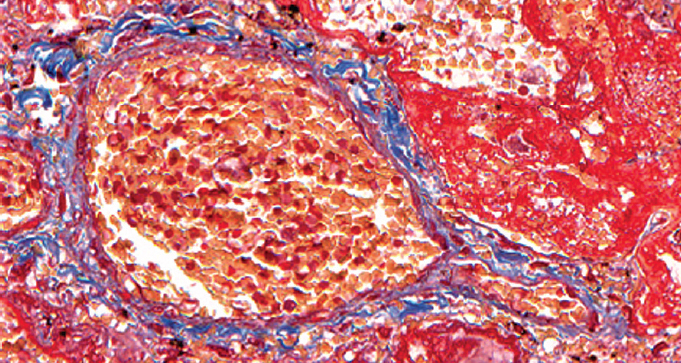

При патологоанатомическом исследовании — ткань легких с диффузными ателектазами, чередующимися с небольшими эмфизематозно расширенными участками, мелкоочаговыми кровоизлияниями в расширенные межальвеолярные перегородки (рис. 1). Большая часть альвеол звездчатой формы, очагово заполнены серозно-фибринозным экссудатом (рис. 2), слущенными альвеолоцитами, альвеолярными макрофагами (рис. 3). Часть альвеол выстлана гиалиновыми мембранами (рис. 4). Сосуды микроциркуляторного русла, расположенные в межальвеолярных перегородках, округлой формы, в просвете большей части которых определяются нити фибрина. Эндотелиальные клетки, выстилающие сосуды, набухшие, овальной формы, другие — более вытянутые, сохраненные не на всем протяжении стенки сосуда. Бронхи среднего и более крупного калибра звездчатой формы, стенка преимущественно утолщена за счет отека и склероза подслизистого слоя. Слизистая оболочка бронхов представлена цилиндрическим эпителием с дистрофическими изменениями, местами слущенным, в сохраненных участках с явлением пролиферации. В просвете бронхиол и более крупных бронхов выявляются десквамированный эпителий, единичные эритроциты, макрофаги. Кроме этого, преимущественно перибронхиально — диффузная лимфоцитарная инфильтрация с примесью умеренного количества нейтрофильных лейкоцитов; разрастание соединительной ткани, образование мелких единичных лимфоидных фолликулов.

Рис. 4. Часть альвеол выстлана гиалиновыми мембранами. Окраска по Массону (трихром). Ув. ×300 / Fig. 4. Part of the alveoli is lined with hyaline membranes. Masson coloring (trichrome). Magnification ×300

Таким образом, впервые описаны морфологические изменения в легких при длительном течении COVID-19 (более 100 сут) у ребенка раннего возраста с ОЛЛ.